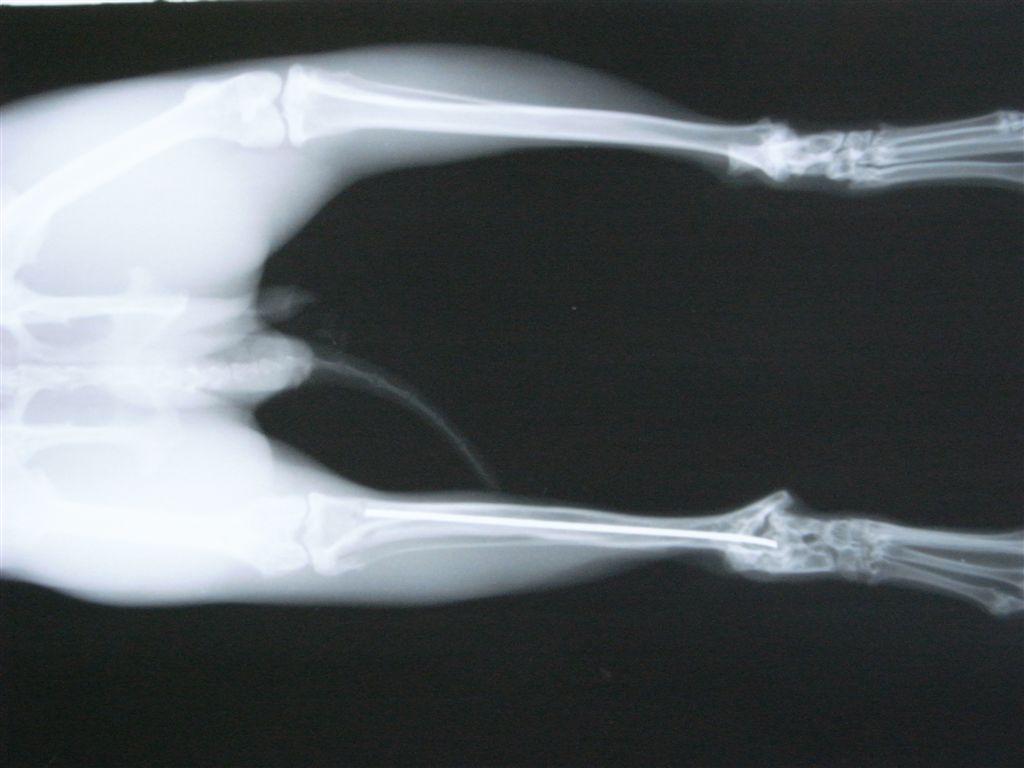

骨折する場所は太股の骨(大腿骨)、すねの骨(頸骨)、背骨(脊椎)です。後ろ足の力が強いために起こります。足の骨の場合、骨の中に金属の棒(ピンニング)やプレートで固定をして外側から固定をして、動かないようにケージに入れておきます(ケージレスト)。1ヶ月から2ヶ月ぐらいかかると思ってください。

右頚骨の骨端線で骨折。

エポキシパテと髄内ピンで整復して固定